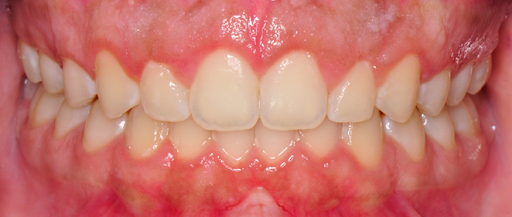

Close-up of a person's upper and lower teeth with appropriately exposed clinical crowns.

After